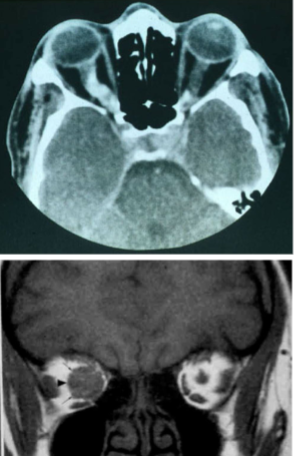

craniopharyngioma

slow growting benign tumors in suprasellar region

arise from remnants of Rathke’s pouch

benign, but locally aggressive

solid + cystic w/ calcification

erosion of dorsum sella

spreading of anterior & posterior clinoids